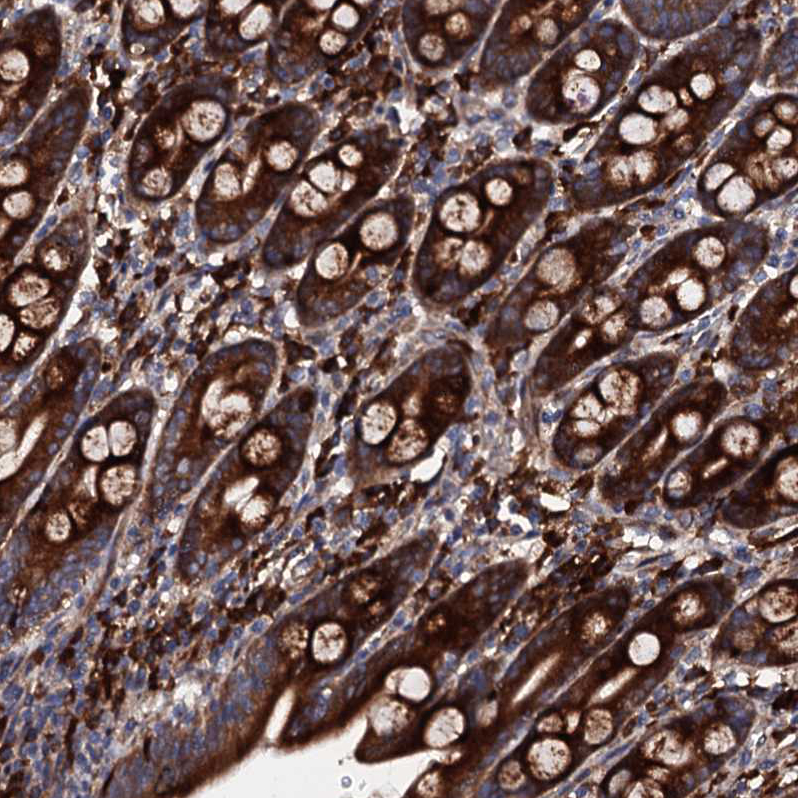

Immunohistochemical staining of human testis shows strong granular cytoplasmic positivity in cells in seminiferous ducts.